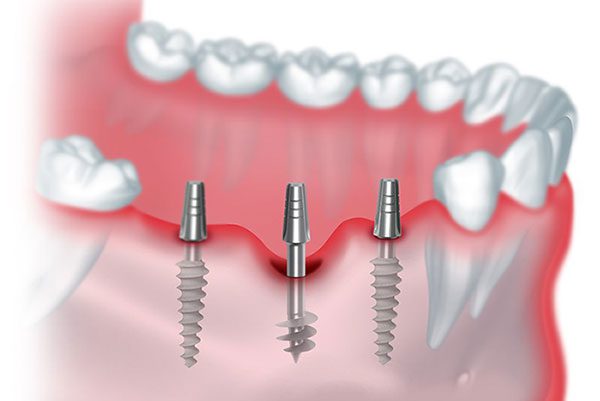

Implants

It’s important to find the right dental care near you. Dr. Renu Dental Clinic, a dental clinic Malviya Nagar, is a great place for people who need reliable dental care. They offer all kinds of treatments in one place. The services are:

With Prime Scan dental, we take accurate 3D images efficiently and comfortably. These scans enable precise planning of crowns, bridges, veneers, splints, and implants, which makes it a perfectly comfortable procedure for the patient.

A good dental clinic in Malviya Nagar should be able to do everything, from fillings and root canals to implants and dentistry for kids. That is why Dr. Renu Dental Clinic can do all kinds of treatments in one place. Moreover, you can find that all these treatments can be done in one day, like in one single sitting, so don’t wait.